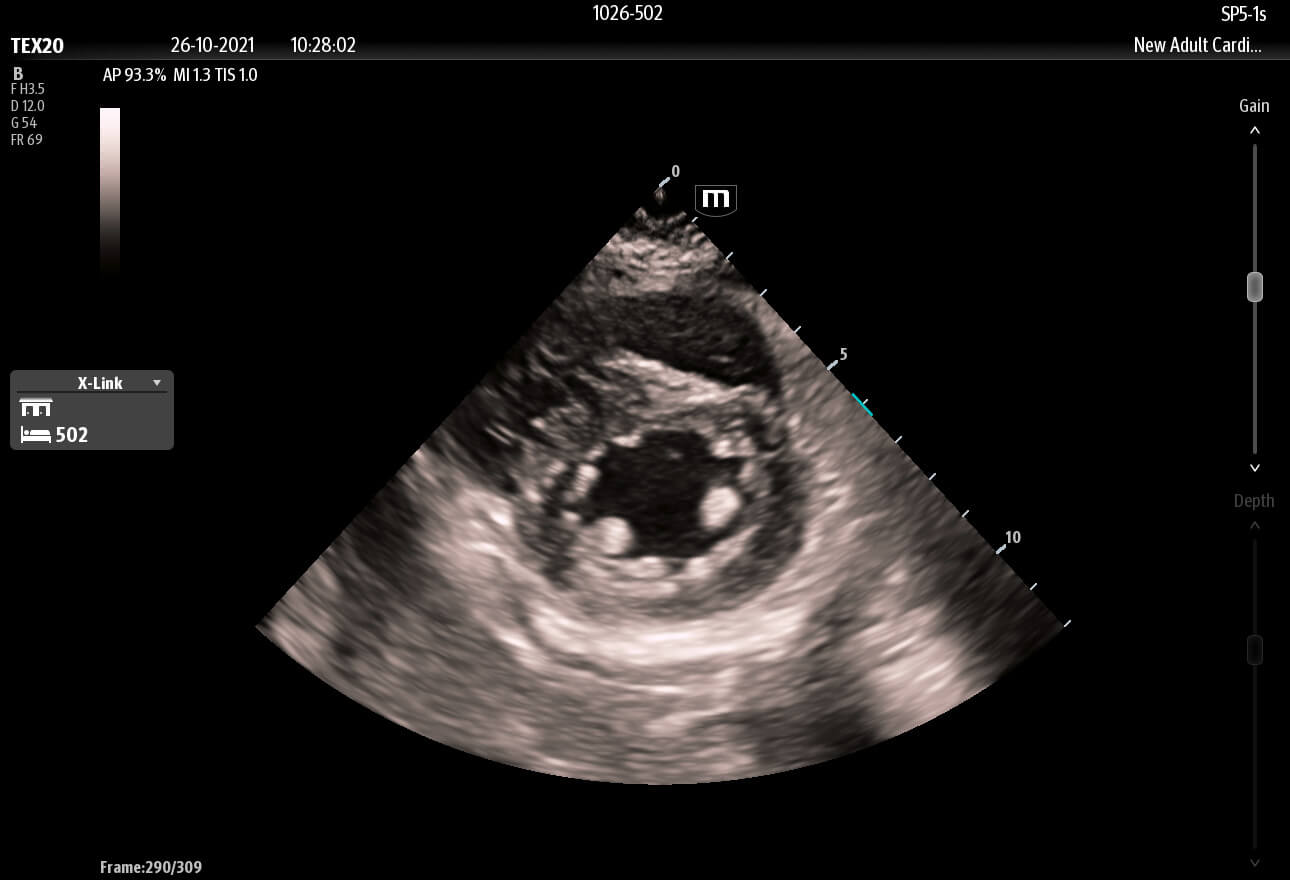

Inspired by the increasing clinical demands of today’s challenging healthcare environment, the touch-based TE X Ultrasound System adopts advanced technologies and integrates them into an innovative, accessible, and patient-centered solution.

The technology-rich TE X Ultrasound System gives clinicians access to market-leading artificial intelligence (AI)-powered Smart Tools, an ergonomically designed system, and proprietary software-based beamformer Zone Sonography Technology+ (ZST+). By incorporating these elements, the TE X Ultrasound System provides access to advanced diagnostic data, the ability to adapt to the various clinical scenarios at point of care, and best-in-class imaging to help them provide a higher standard of care.